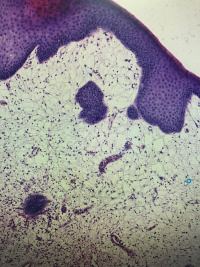

尿道肉阜

性别

女

年龄

62

临床诊断

一般病史

尿道流血3年

标本名称

大体所见

灰白组织一块,大小1.2✖️0.8✖️0.8,切面灰白,半透明,质软

符合:

尿道肉阜。